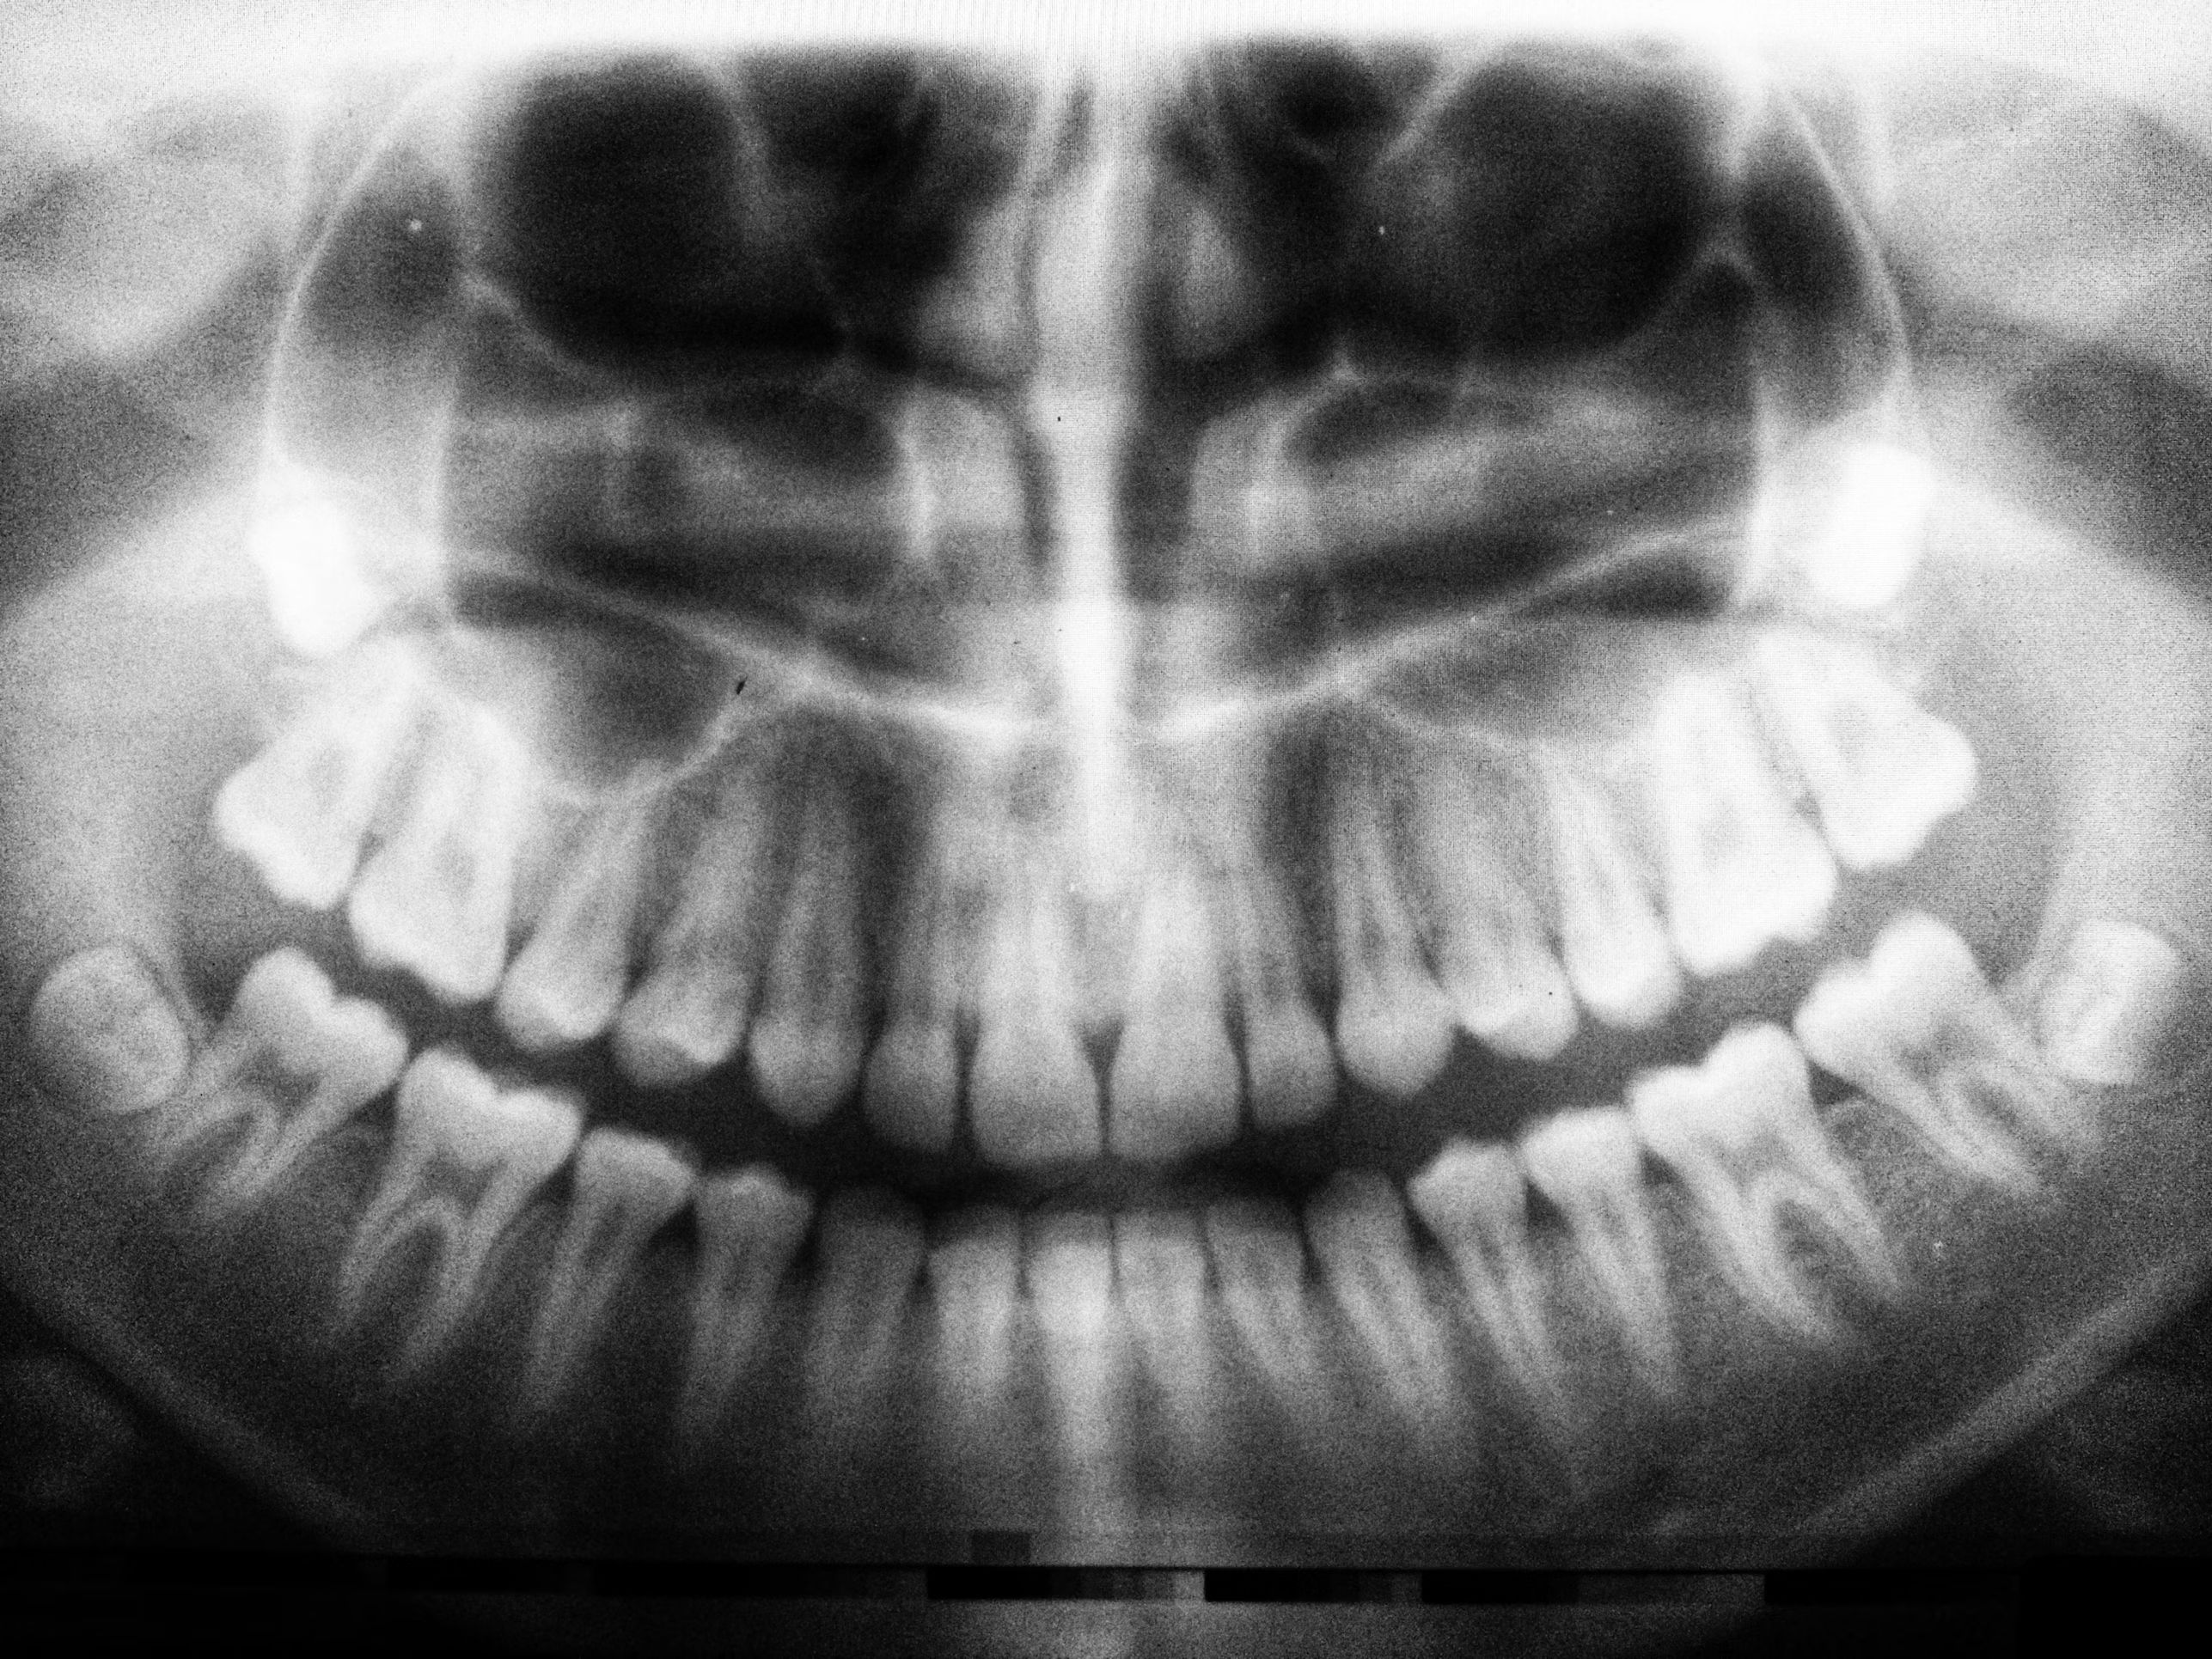

Your dentist can examine the tooth, take X-rays, and recommend the most appropriate treatment to relieve pain and protect your oral health.